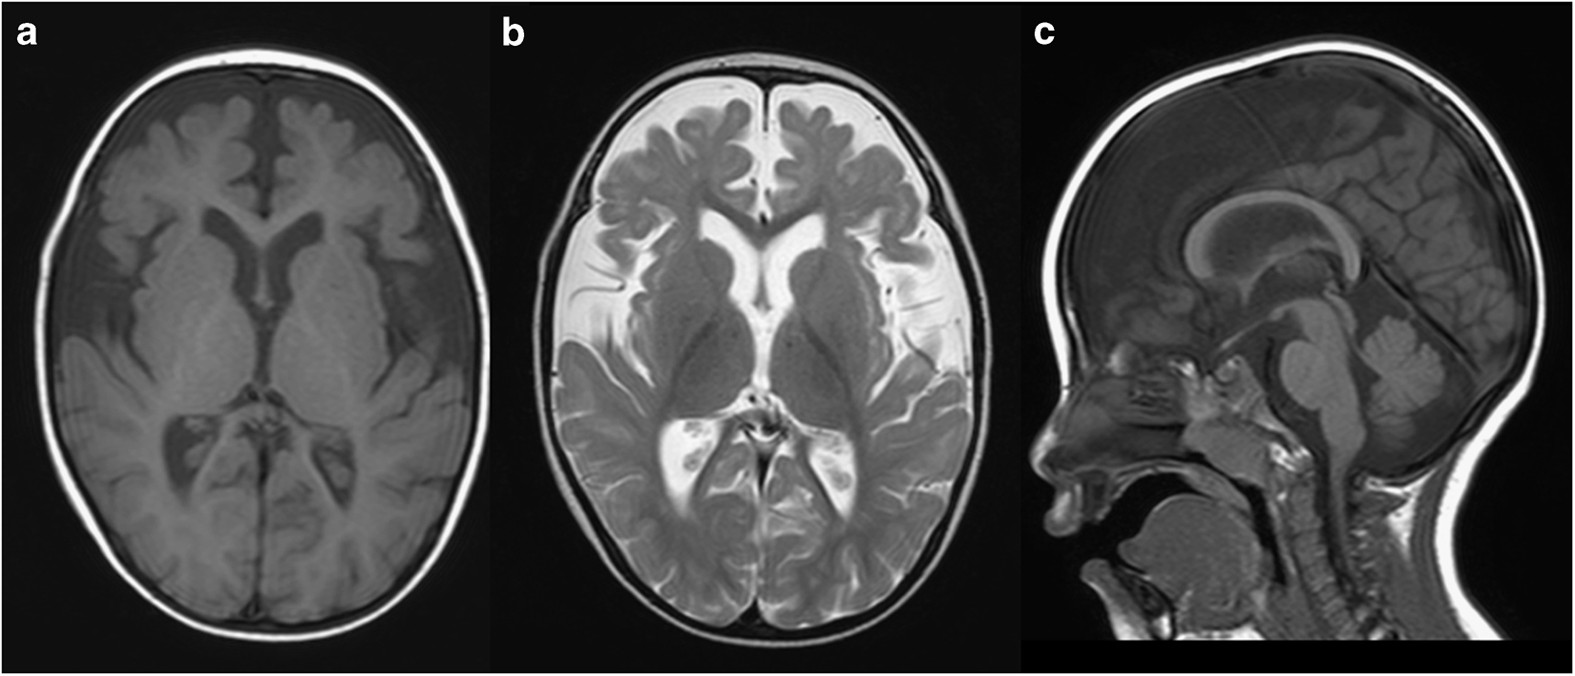

Brain magnetic resonance imaging examination at 2 years of age. Axial T1- and T2-weighted images (a and b, respectively) and a sagittal T1-weighted image (c). Decreased volume of the cerebrum (a, b) and delayed myelination in the deep white matter (b) are evident. The volume of the corpus callosum is also reduced (c).